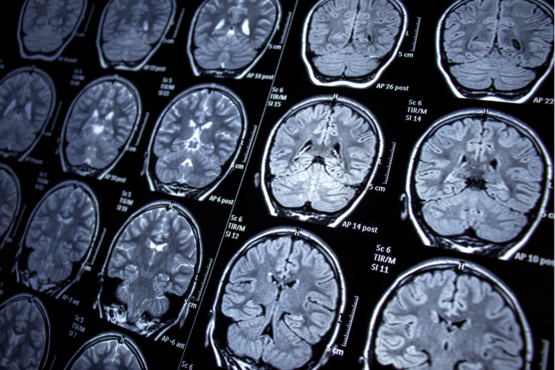

Tiefe Hirnstimulation: Für wen, wie wird es gemacht?

Die tiefe Hirnstimulation (THS, DBS) ist ein anerkanntes Routine-Verfahren, das bei Parkinson-Patienten vor allem bei Off-Phasen und Levodopa-Wirkungsschwankungen hilfreich sein kann. In diesem Vortrag wird erläutert, nach welchen Kriterien Patientinnen und Patienten für die Therapie ausgewählt werden, wie die Operation abläuft und welche technischen Entwicklungen (z. B. neue Elektroden und Stimulationsverfahren) die Behandlung verbessern. Auch mögliche Risiken sowie Nachsorge und langfristige Erfahrungen kommen zur Sprache. Ziel ist es, Betroffenen, Angehörigen und nicht-spezialisierten Ärzten einen fundierten Überblick über Chancen und Grenzen dieser modernen Therapieoption zu bieten.